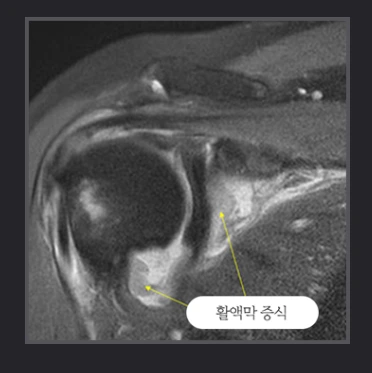

류마티스 관절염에 의해 어깨관절 활액막에 염증이 생겨 활액막이 증식 비후 되고 관절의 부종이나 통증이 발생하는 질환입니다. 약물치료에 반응하지 않는 경우에는 관절연골의 손상을 막기 위해 관절내시경을 이용한 활액막제거술을 시행하지요.

류마티스성관절염.PNG